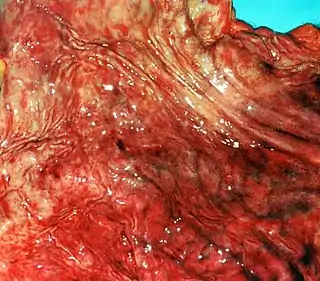

![]() Gastritis erosiva | ||

- Gastritis erosiva. Se caracteriza por erosiones superficiales y múltiples en la mucosa del estómago, suele producirse por ingesta de antiinflamatorios no esteroideos y puede provocar la aparición de hemorragia digestiva. En algunos casos puede evolucionar a úlcera péptica.